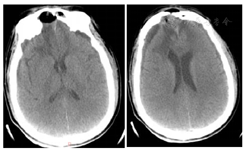

患者于伤后当天(2021年7月29日)在当地医院急诊行"颅内血肿清除术+凹陷性粉碎颅骨骨折清除术",术后持续出现脑脊液鼻漏,伴伤口渗液,持续昏迷,GCS评分E1VTM3。患者于2021年8月3日转入我院,于2021年8月5日在全麻下行"颅骨骨折整复+脑脊液漏修补术",开颅探查前颅底进行重建修补,额窦及筛窦存在裂缝,封填额窦和筛窦,并取大腿部部分阔筋膜、少量脂肪和肌肉填塞,术中见额部硬膜存在缺损,以人工脑膜进行严密缝合,留置皮下引流管,术后第3天引流量少,皮下引流管拔除。术后观察患者未再出现脑脊液漏。术后仍为昏迷状态,住院期间,间断出现发热,热型表现为不规则热。2021年8月8日行腰椎穿刺术并留取脑脊液检查,提示:WBC:83×106/L,葡萄糖<1.0 mmol/L,乳酸5.62 mmol/L,氯106.7 mmol/L,蛋白质1.19 mmol/L;脑脊液培养结果为:鲍曼氏不动杆菌;痰涂片可见革兰阳性球菌、阴性杆菌;考虑颅内感染并呼吸道感染。根据药敏结果给予以替加环素100mg、每12小时1次,联合万古霉素1.0g、每12小时1次抗感染治疗。患者仍存在持续高热,2021年8月10日行"腰大池置管外引流术",有黄色透明脑脊液流出,复查脑脊液结果提示:WBC:37×106/L,蛋白质1.18 mmol/L。2021年8月12日呼吸道标本培养提示:鲍曼氏不动杆菌,调用抗生素为多黏菌素50u、每12小时1次,联合替加环素100mg、每12小时1次,利奈唑胺600mg、每8小时1次,治疗呼吸道感染及预防革兰阳性球菌所致颅内感染。2021年8月16日患者意识呈昏迷状态,刺激能睁眼,体温间断高热,腰大池引流不通畅给予拔除。头部伤口愈合差,有少量脓性渗出,若进一步发展,有加重颅内感染可能,头部伤口给予留置VSD(图3)辅助伤口愈合。抗生素应用方案为多黏菌素50u、每12小时1次,替加环素100mg、每12小时1次,利奈唑胺600mg、每8小时1次。2021年8月17日复查脑脊液结果提示:WBC:350×106/L,蛋白质2.37 mmol/L,2021年8月19日患者呈浅昏迷状态,刺激可睁眼,患者痰培养、血培养、伤口分泌物培养均未见菌种生长,停用替加环素。体温较前稳定,感染基本控制。2021年8月24日复查脑脊液结果提示:WBC:8×106/L,蛋白质0.7 mmol/L,细菌培养未检出。查血清G试验结果为阴性GM试验<0.5 µg,肺泡灌洗液细菌培养未见菌种生长。复查头部CT示双侧额叶出血及水肿较入院时吸收,硬膜下少量积液(图4)。患者意识状态较前改善,回当地医院继续康复及支持治疗。

2022年4月11日,患者头颅CT提示脑积水较前较少(图6),患者GCS评分15分,MMSE评分21分,认知功能改善至轻度认知功能障碍。2022年5月17日,行"颅骨修补术"(图7)。术后1个月,患者GCS评分15分,MMSE评分27分,认知功能改善至正常。